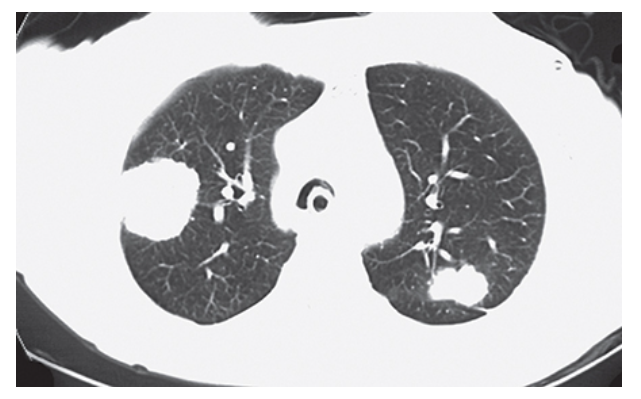

Histoplasmosis. Axial CECT shows two well-ground glass nodules in the right mid lung in a patient with histoplasmosis.